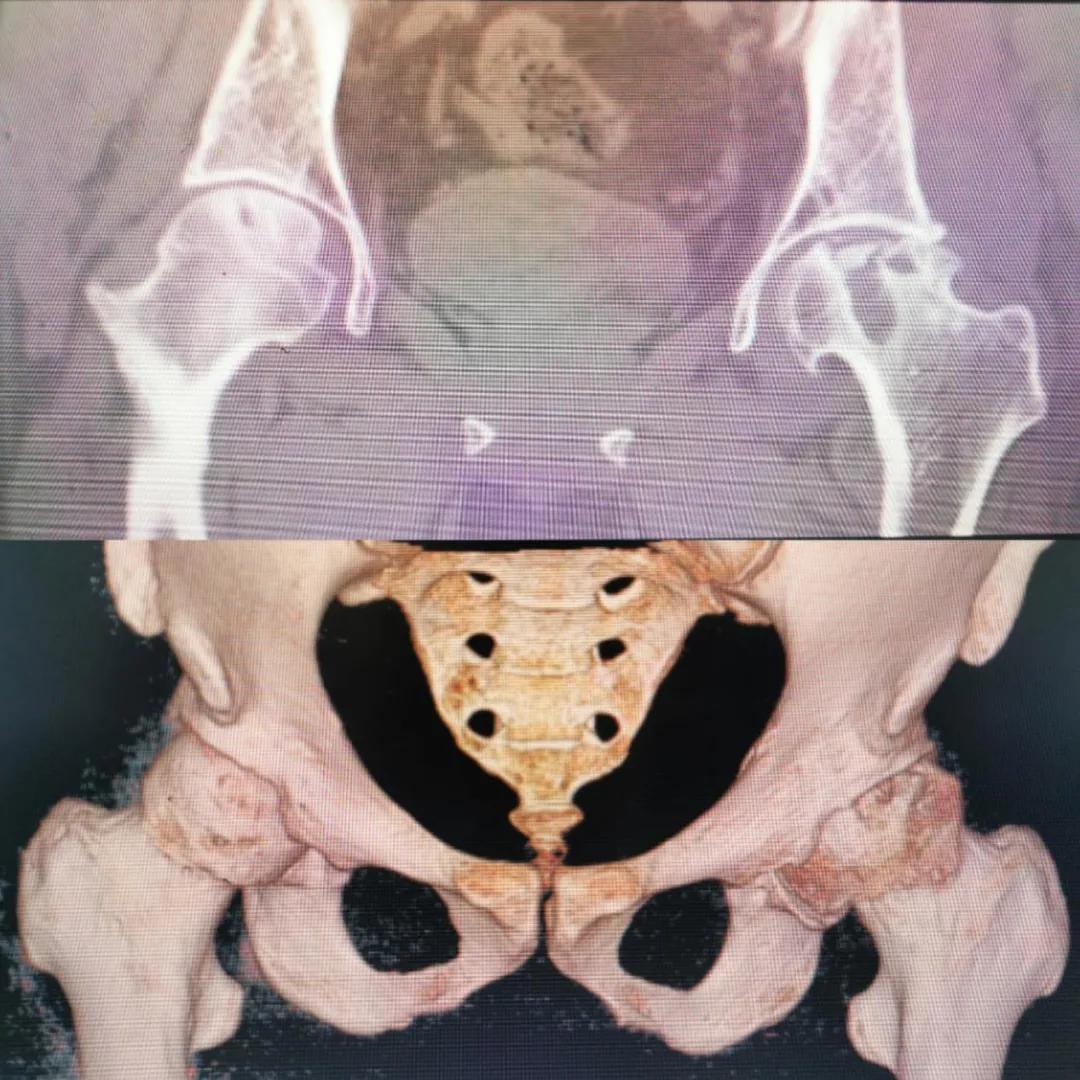

入院急查血結(jié)果提示炎癥反應(yīng),感染較重,凝血功能及肝功均不同程度損害;髖關(guān)節(jié)磁共振(MRI)檢查提示雙側(cè)股骨頭缺血壞死,繼發(fā)髖關(guān)節(jié)炎,左側(cè)髖周軟組織腫脹。醫(yī)療團(tuán)隊(duì)給出的初步診斷為膿毒血癥、股骨頭缺血性壞死、軟組織感染、皮膚潰瘍及閉孔神經(jīng)損傷。

圖片(圖為患者入院時(shí)髖部CT檢查)

追溯病史,患者訴前不久曾用蜂蜇療法治療股骨頭壞死,每日4次,每次100只蜜蜂蜇雙臀部、髖部,這才導(dǎo)致了病情急劇進(jìn)展。查明了來龍去脈,我院智能微創(chuàng)骨科醫(yī)護(hù)團(tuán)隊(duì)與患者家屬積極溝通病情,給予特殊級抗生素抗感染以及消腫、止痛等支持治療,同時(shí)對潰瘍創(chuàng)面進(jìn)行專業(yè)、規(guī)范的清創(chuàng)、換藥處理,保護(hù)創(chuàng)面降低感染程度;護(hù)理上輔助翻身,減少壓力性損傷。